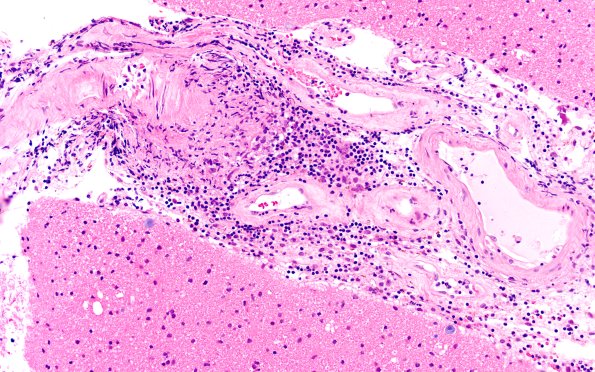

Washington University Experience | VASCULAR | Vasculitis - PACNS | 17B6 Vasculitis (Case 17) H&E 20x 2

Leptomeningeal vessels encountered were typically larger than parenchymal vessels and showed a similar lymphohistiocytic infiltrate, in some cases superimposed on thickened hyalinized small vessels. (H&E)